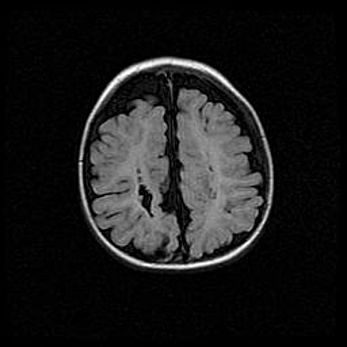

Открытая гидроцефалия.

Возраст: 9 месяцев 12 дней

Вес: 6800 г

Пол: мужской

Окружность головы: 41,5 см

Срок гестации: 28 недель

Гидроцефалия головного мозга у новорожденных имеет характерный признак: опережающий рост окружности головы приводит к визуально хорошо определяемой гидроцефальной форме сильно увеличенного в объёме черепа. Детские неврологи определяют следующие симптомы гидроцефалии у грудничков: выбухающий напряжённый родничок, частое запрокидывание головы, смещение глазных яблок к низу.